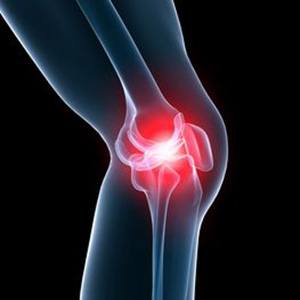

Knee Pain

Knee pain is a common condition affecting individuals of various age groups. It not only affects movement but also impacts your quality of life.